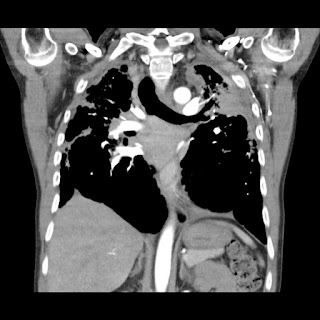

Hombre de 61 años asintomático. Colonoscopia demuestra válvula ileocecal ulcerada y estenótica. No hay antecedente de Enfermedad Inflamatoria Intestinal.

Con base en lo anterior el siguiente paso a seguir es?

a) Valoración por cirugía general.

b) Iniciar tratamiento con anti-inflamatorios e inmunosupresores.

c) Biopsia bajo guía ecográfica de las lesiones focales hepáticas.

d) Repetir colonoscopia.